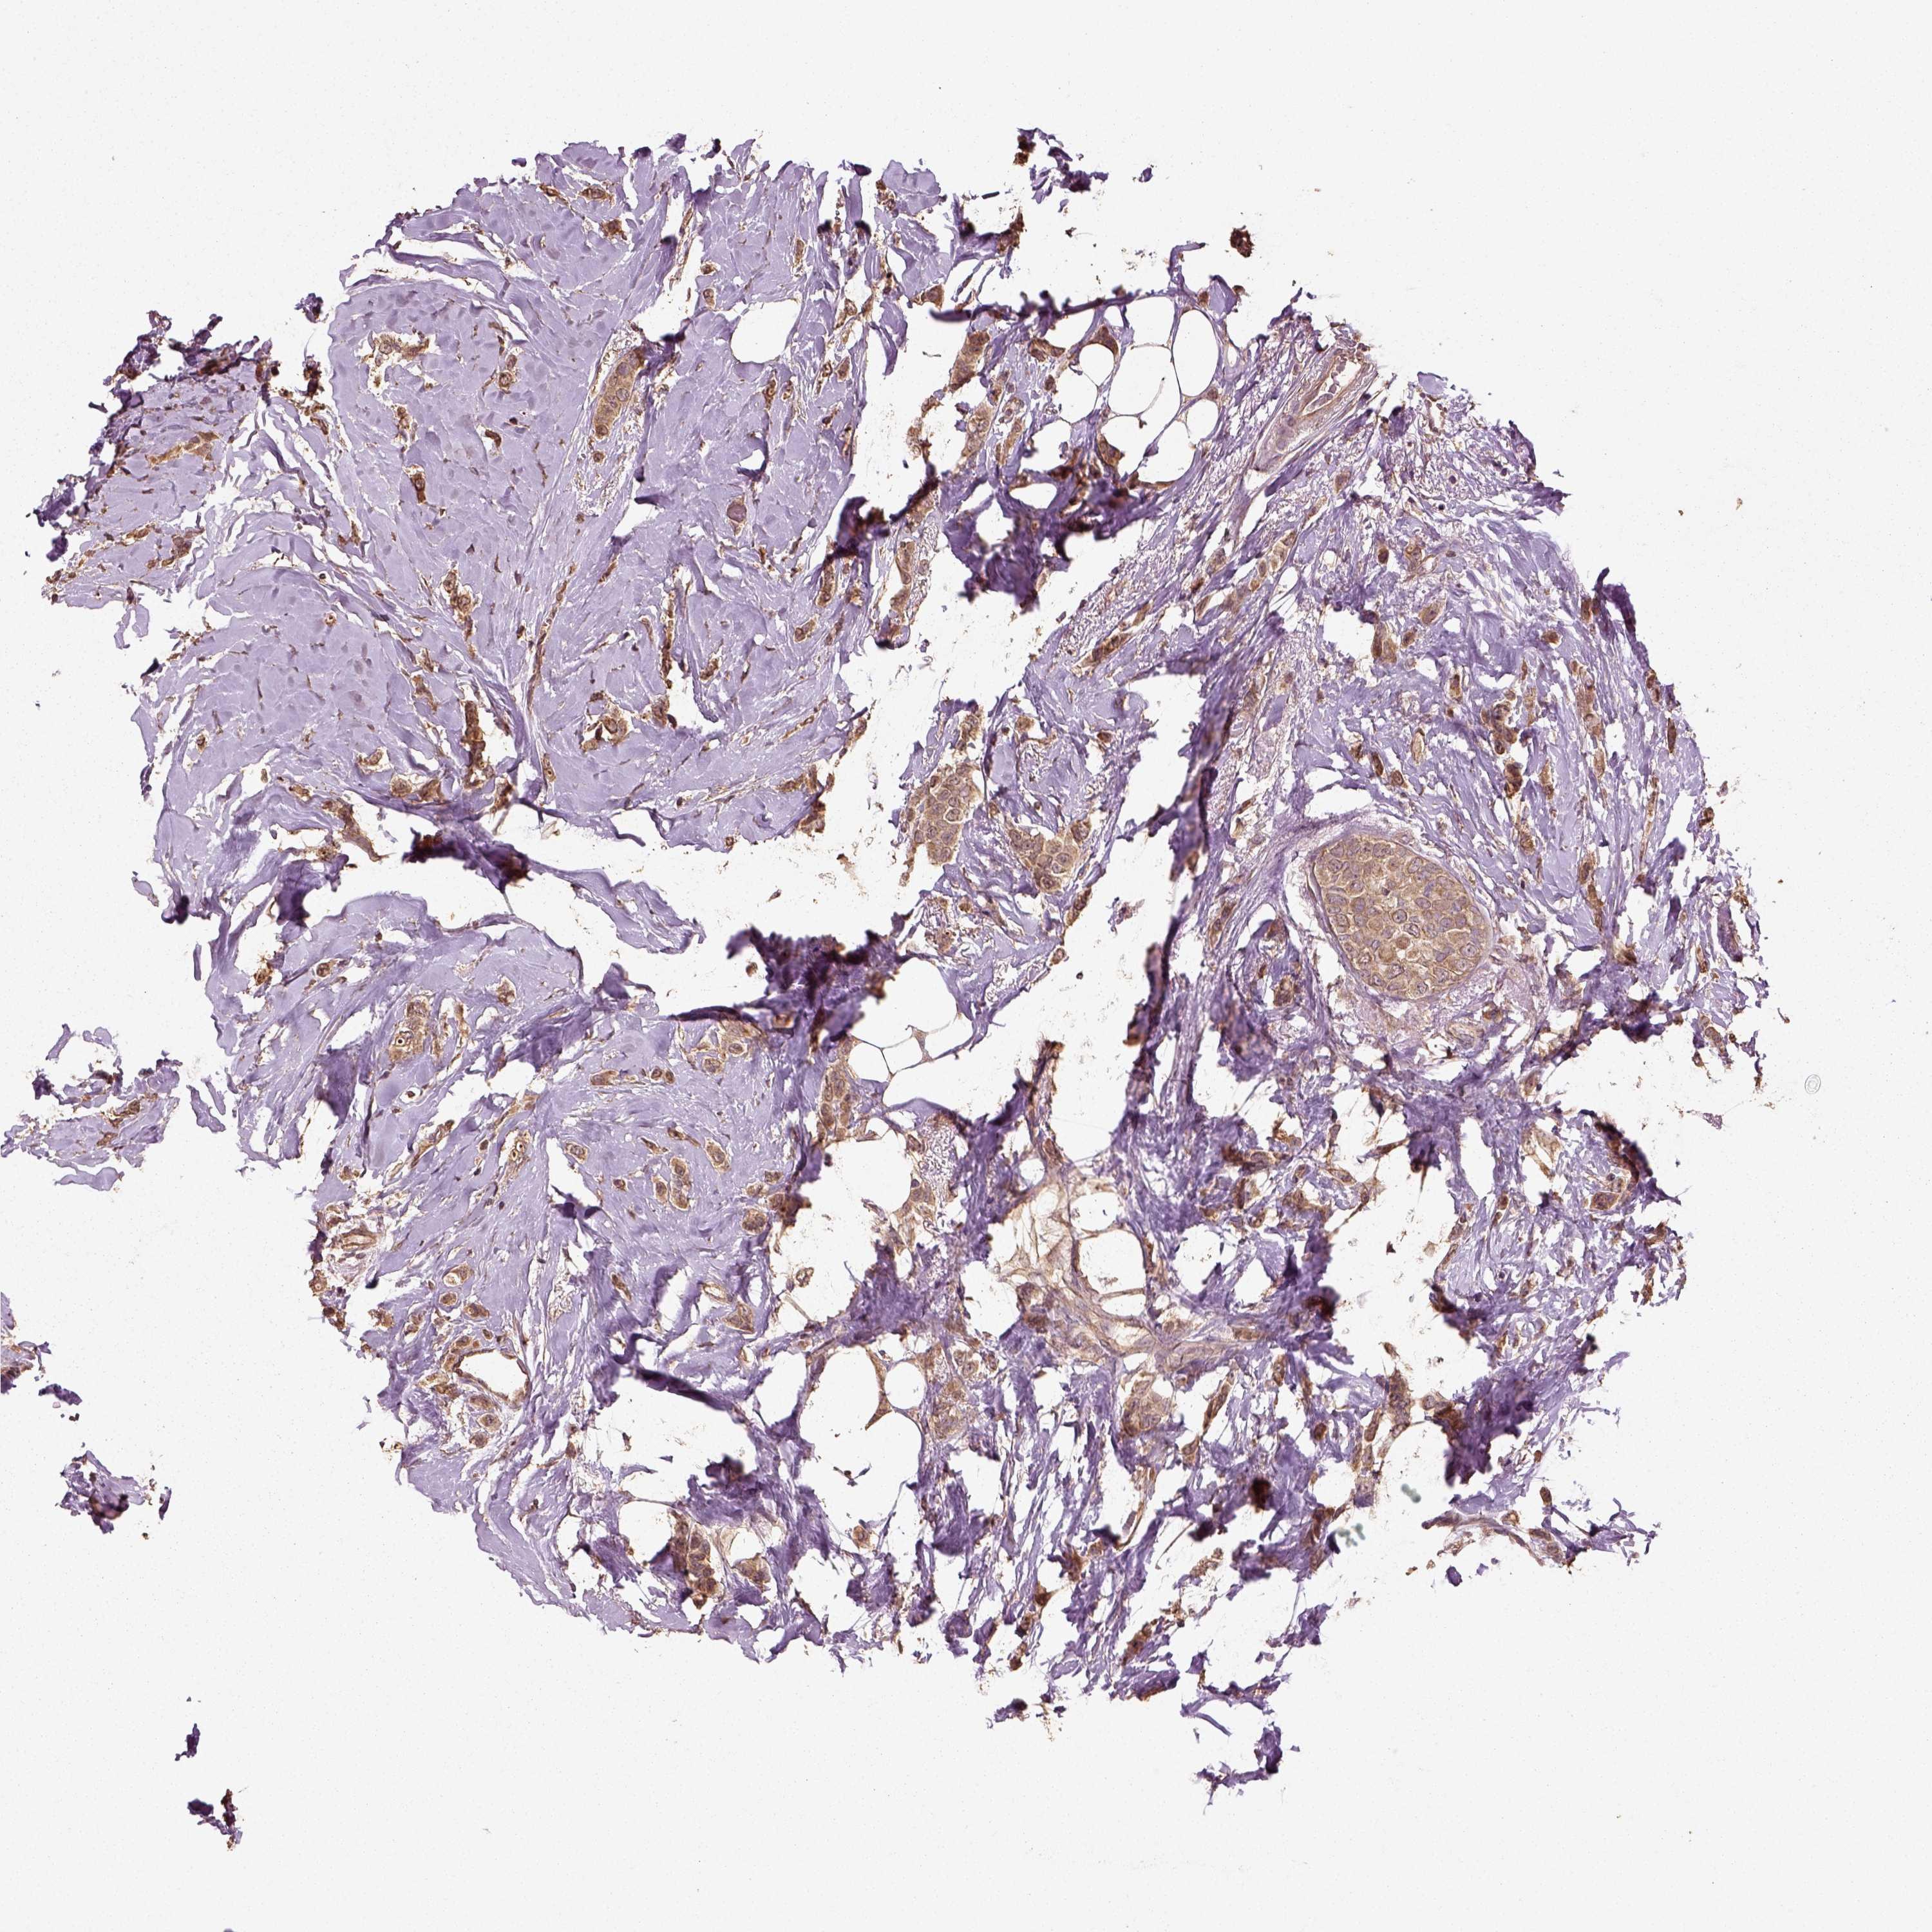

CANCER BREAST CANCER Show tissue menu

BRCA TCGA BRCA VALIDATION PROTEIN EXPRESSION